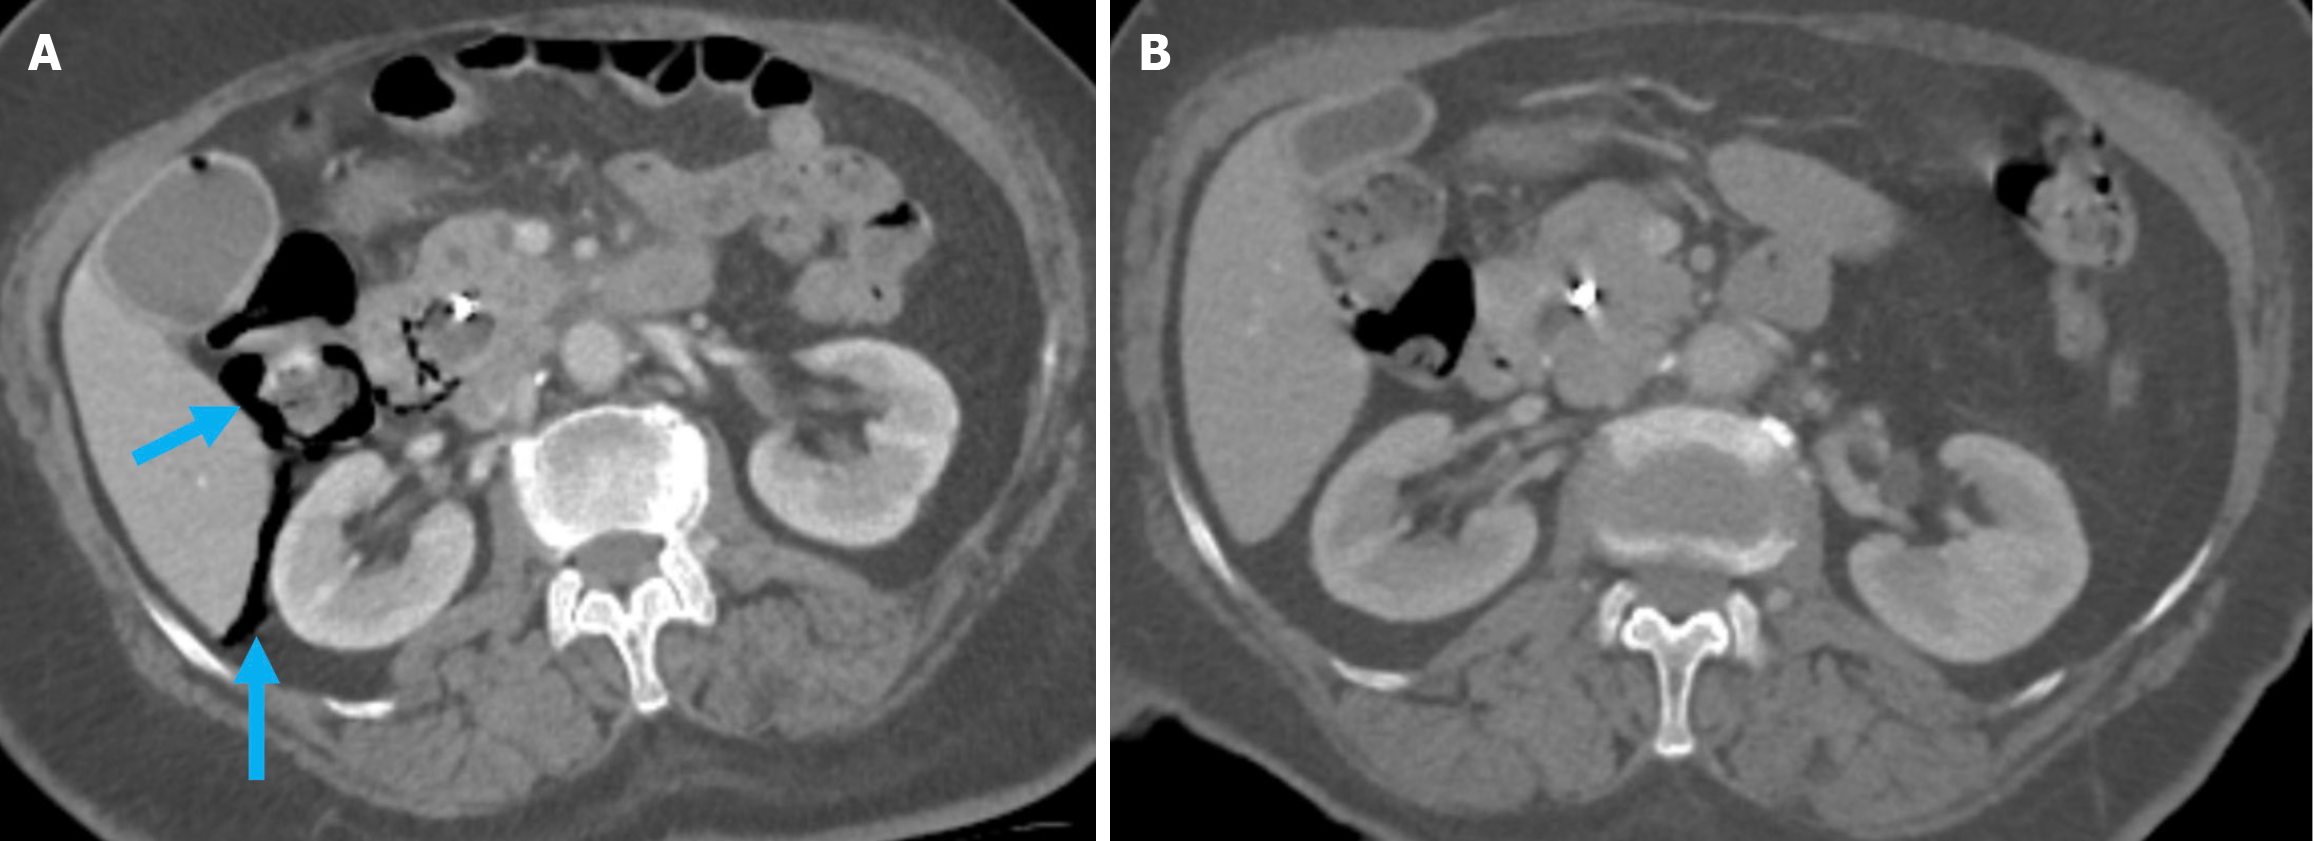

The revised Atlanta classification recognizes two primary forms of acute pancreatitis: NP and interstitial edematous pancreatitis (IEP). NP tends to follow a more severe clinical course with higher rates of infection, organ failure, and mortality. Imaging reveals hypoperfused or non-enhancing areas indicating NP or peripancreatic necrosis. Early collections (within 4 weeks) are referred to as acute necrotic collections. Once encapsulated after 4 weeks, they are known as walled-off necrosis (Figure 3)[23]. IEP is characterized by a diffusely enlarged pancreas with homogeneous enhancement on CECT imaging without areas of necrosis and with peripancreatic fat stranding and fluid accumulation. Fluid collections observed within the first 4 weeks are termed acute peripancreatic fluid collections, while those persisting beyond 4 weeks are classified as pancreatic pseudocysts (Figures 4 and 5).

Figure 5

Figure 5 Acute peripancreatic fluid collections and pseudocyst. A: Noncontrast axial computed tomography (CT); B: Contrast-enhanced axial CT after 15 months. A 28-year-old female patient underwent endoscopic retrograde cholangiopancreatography for choledocholithiasis. Ten hours after the procedure, the patient developed severe upper quadrant abdominal pain accompanied by fever. No signs of peritonitis were observed, and there was no evidence of hemodynamic instability. Laboratory tests revealed elevated levels of pancreatic enzymes and inflammatory markers. Due to suspected pancreatitis a noncontrast CT performed on post-procedure day 1 (A) demonstrated fluid loculation in the infrahepatic and paraduodenal region that was consistent with acute peripancreatic fluid collections (yellow arrow). The patient was diagnosed with post-endoscopic retrograde cholangiopancreatography edematous pancreatitis and was managed conservatively. A follow-up contrast-enhanced CT performed 1.5 months later (B) showed fluid collection in the exact location with pseudocapsule formation that was consistent with a pseudocyst (blue arrow).